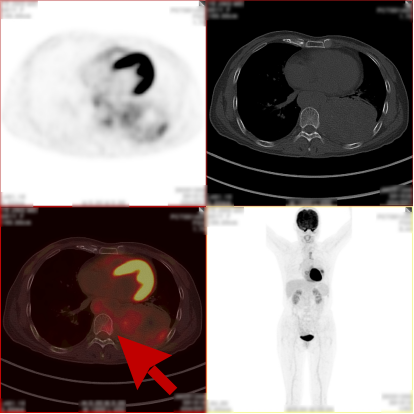

病史:女,51岁,左侧胸腔肿物约3-4年,干咳伴左侧胸痛1个月余,自服药物不能缓解。2023.12.6 CT 显示左侧胸腔及纵隔内肿块,考虑肿瘤性病变,胸膜来源低度恶性肿瘤(胸膜间皮瘤)可能。无其他病史,进食可,二便可,今年以来有体重减轻,为鉴别病灶良恶性申请PET/CT检查。

PET/CT检查所见

PET/CT诊断意见:

1、左侧胸腔内混杂密度肿块,实性组织代谢轻中度增高,考虑间叶组织来源低度恶性肿瘤,病灶内部分组织坏死,与左侧胸膜粘连并向纵隔内生长;

2、纵隔(1L、2L、3A、6、8R 组)及左侧锁骨上窝多发淋巴结转移灶;

3、胸 8 椎体左份结节状高代谢病灶,考虑骨转移灶。

PET/CT活检病理:恶性畸胎瘤